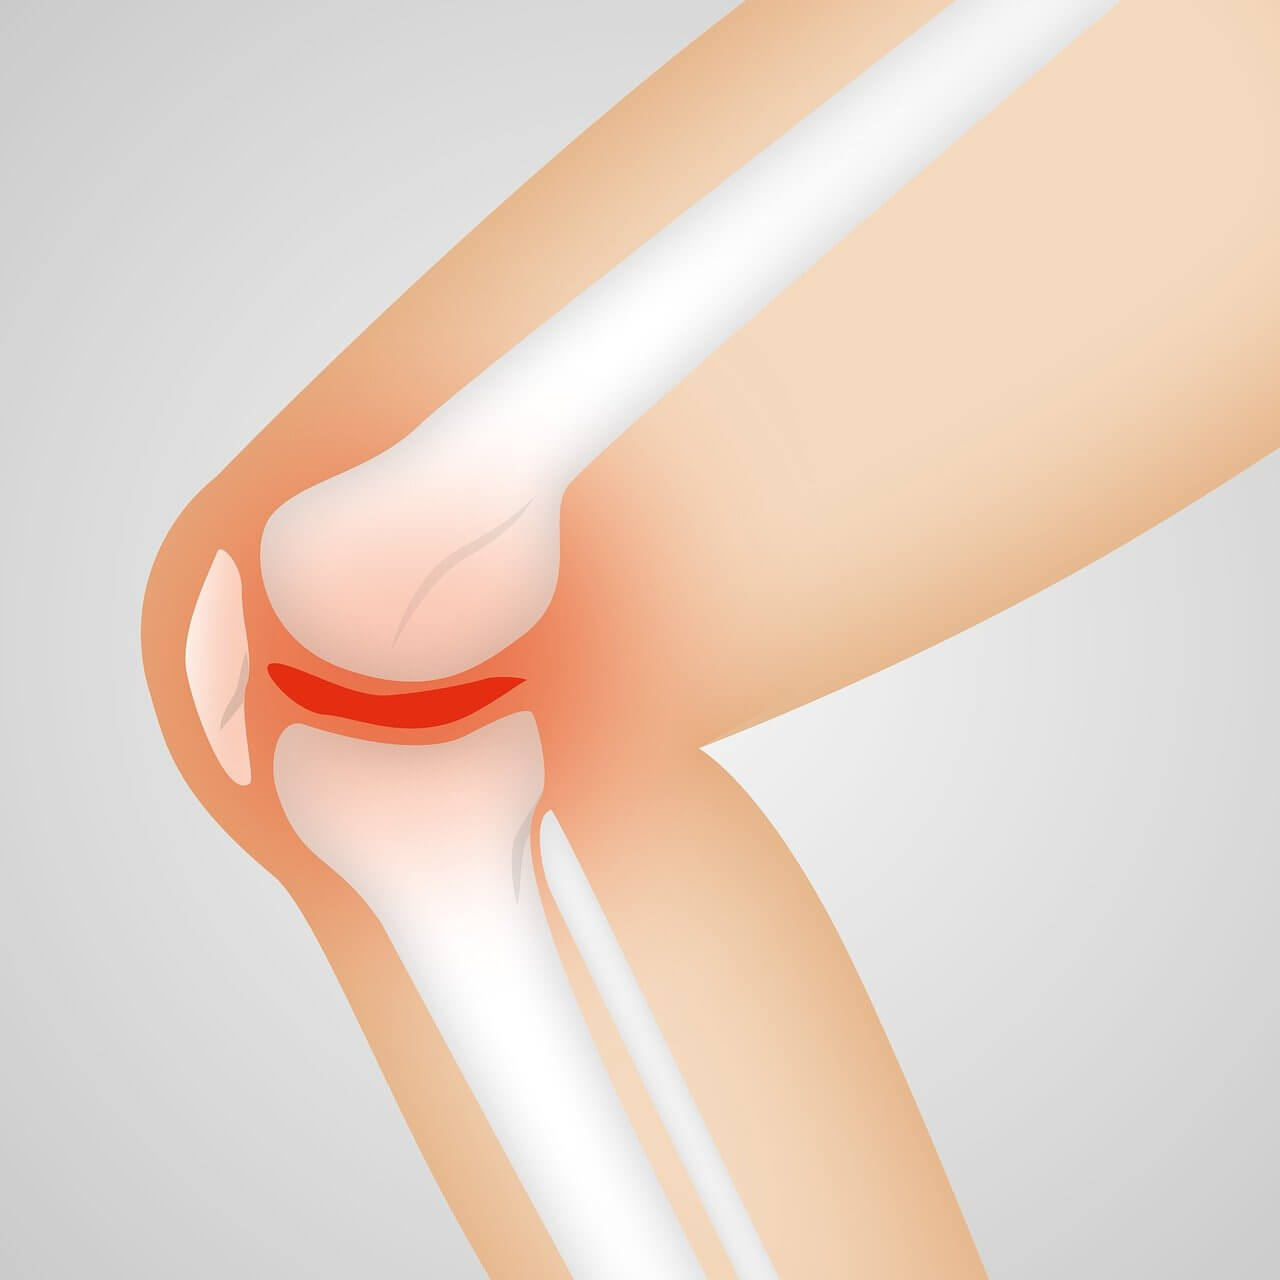

퇴행성 관절염은 무릎 관절 사이의 연골이 마모되면서 관절면이 서로 맞닿아 통증과 염증을 유발하는 질환입니다. 나이가 들면서 자연스럽게 발생하기도 하지만, 비만, 무리한 운동, 무릎 부상 등이 무릎통증 원인이 될 수 있습니다. 연골은 신경이 없어 아프지 않지만, 마모되면서 주변 뼈와 조직에 염증을 일으켜 무릎통증이 나타나는 것입니다.